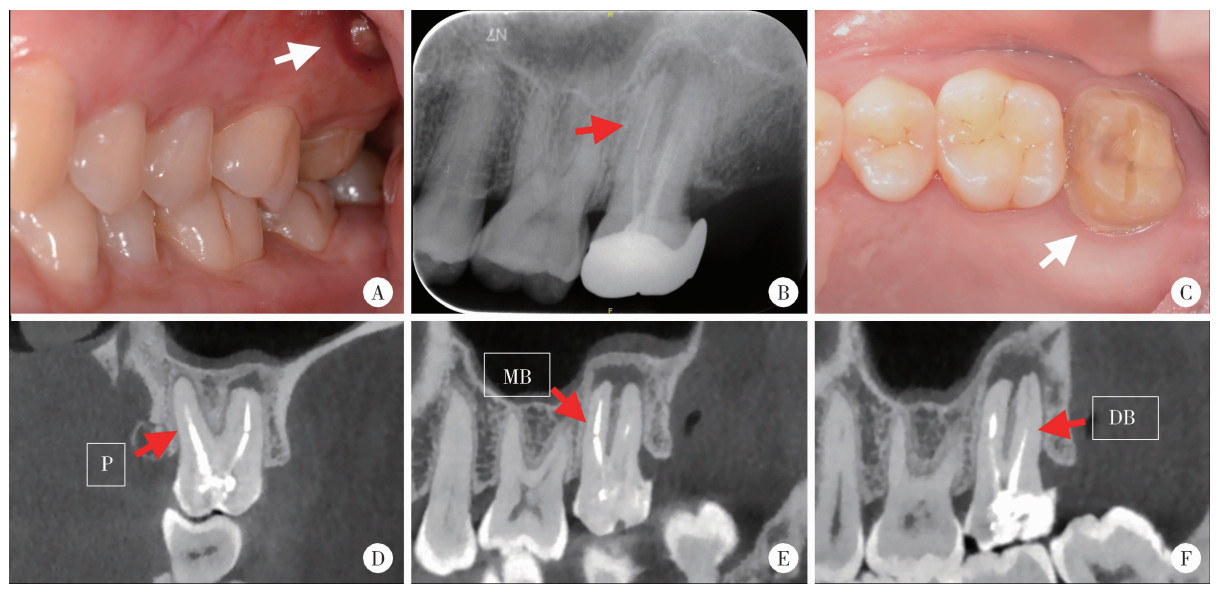

Figure 1

Intraoral examination, preoperative radiograph and cone-beam CT images of left maxillary second molar A, preoperative intraoral view of apical swelling (white arrow); B, preoperative periapical radiograph shows a metallic high-density fractured instrument (red arrow) within the mesiobuccal canal; C, the clinical view after crown removal reveals a resin filling and a palatal fiber post (white arrow); D, the palatal post extends to the mid-root level with an apical radiolucency; E, the image confirms the separated instrument in the apical third of the mesiobuccal root, associated with an apical radiolucency communicating with the distobuccal apical lesion; F, underfilled obturation is observed in the distobuccal root canal. P, palatal; MB, mesiobuccal; DB, distobuccal."